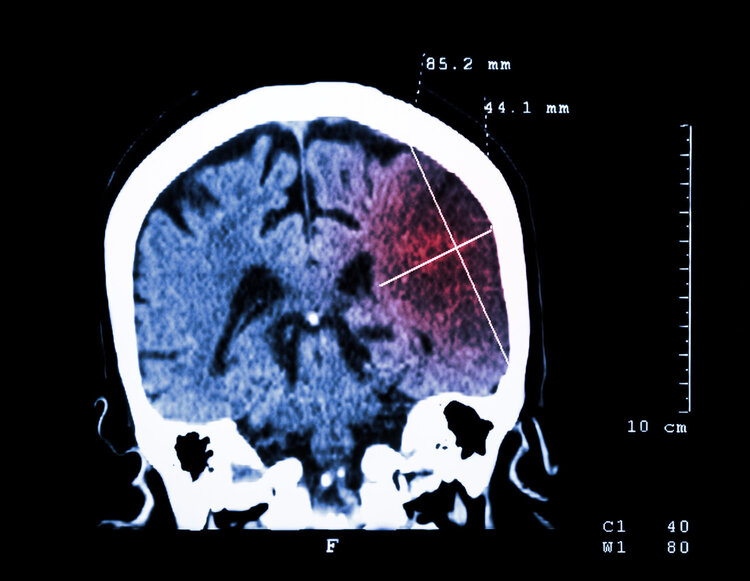

第二天,縣醫(yī)院對王姥姥進行頭顱CT檢查提示其腦干出血,住院搶救48小時無效死亡。